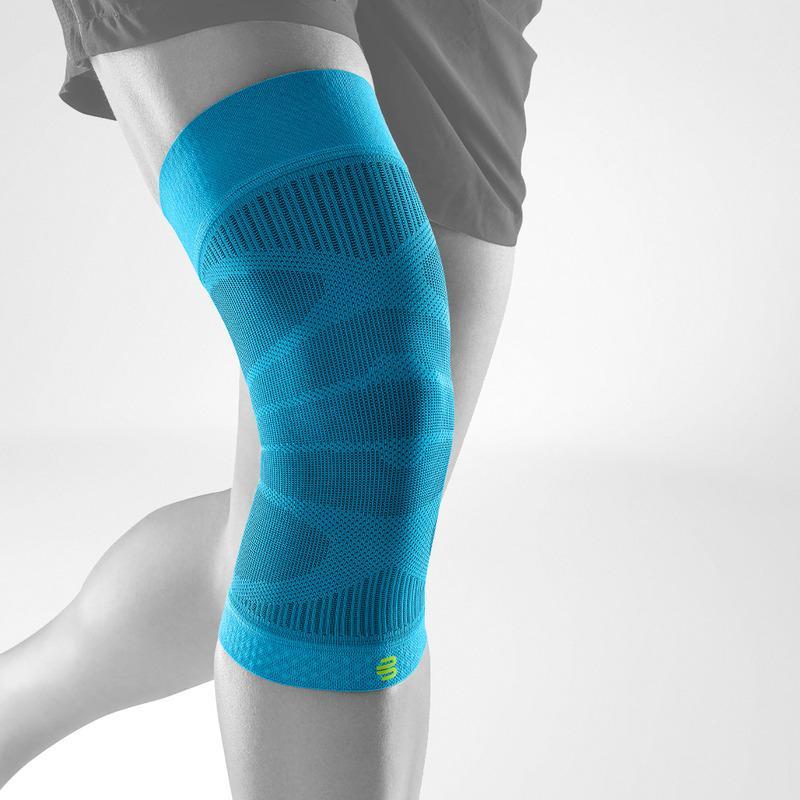

Om man behandlar konservativt är vila avgörande och lika viktigt som kontrollerad och riktad förstärkning. Användningen av kryckor, stabiliserande stöd och hängslen och antiinflammatoriska mediciner kan alla användas för att påskynda återhämtningen.

Meniskopati - Lindra smärta med stöd och hängslen

Om det finns smärta, svullnad eller instabilitet i knät är fördelen med knästöd överväldigande. Genom att bära GenuTrain-serien (varierar beroende på skada), fungerar den riktade kompressionen och gelstödet effektivt för att lindra dessa problem och återhämta knät snabbt efter operationen.